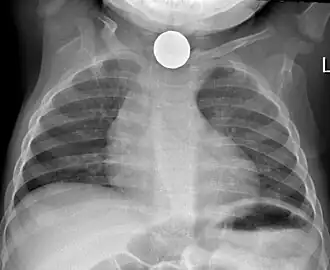

Chest x-ray in an infant showing aspiration of a metallic coin without signs of mediastinal shift.

Foreign body aspiration is a major cause of death in young children due to their underdeveloped swallowing coordination. Young children most commonly ingest toys, coins, or food.[21] On chest x-ray, the most frequent sign is air trapping that can lead to a mediastinal shift. Atelectasis and pneumothorax may also occur in the setting of foreign body aspiration. The diagnosis is made in conjunction with clinical symptoms and confirmed and treated with bronchoscopy.[22]